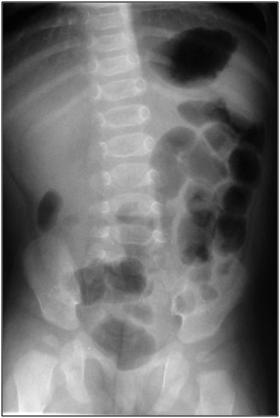

Kontraindikasi reduksi radiologis adalah adanya tanda-tanda dehidrasi, syok, peritonitis atau dari pemeriksaan radiografi adanya tanda-tanda udara bebas. Tatalaksana operasi secepatnya dilakukan bila terdapat tanda-tanda udara bebas. Terdapat beberapa factor yang dapat mereduksi kesuksesan reduksi radiologis yaitu usia (< 6 tahun), perdarahan rektum, tanda-tanda obstruksi usus, atau pemanjangan durasi gejala (72 jam). Pemilihan teknik reduksi , hidrostatik atau pneumatic, fluoroskopik atau sonographik bergantung terhadap pengalaman dan pilihan dari dokter yang melakukan.